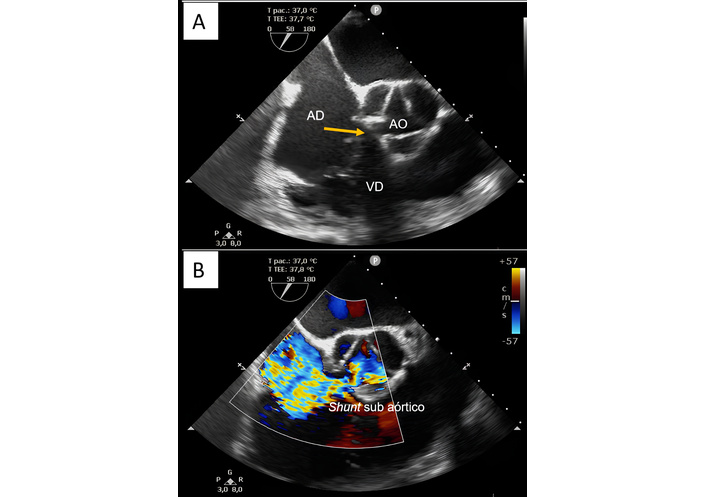

A transesophageal echocardiogram was performed, which demonstrated a 74% LV ejection fraction, enlargement of the right cavities and LA, communication between the LV (subaortic region) and the RA of 6 to 8 mm with a maximum gradient of 56 mmHg, left-to-right shunt (Figure 2), in addition to moderate tricuspid regurgitation and estimated pulmonary artery systolic pressure of 50 mmHg.

Transesophageal echocardiogram without (A) and with color doppler (B) showing enlargement of the right atrium, communication between the left ventricle (subaortic region) and the right atrium of 6 to 8 mm with a maximum gradient of 56 mmHg. In (A), the yellow arrow indicates the Gerbode defect (AO: aorta; AD: right atrium; VD: right ventricle); in (B), the left-to-right subaortic shunt is observed from the pulsed Doppler.